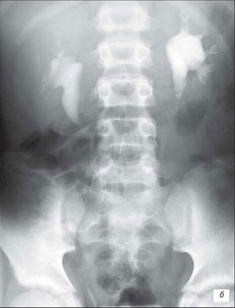

Рентгенограма хворих з СМР

При 1‑й степені закид контрасту з сечового міхура походить тільки в нерозширений сечовід.

При 2‑й степені заповнюють нерозширений сечовід і нерозширений чашечко-мискова система (ЧМС) нирок.

При 4‑й степені і вони стають заокругленими.

При 5‑й степені характеризується масивною делятацією і звивістю верхніх сечових шляхів.

Екскреторна урографія хворого з двостороннім обструктивним мегауретритом

На екскреторній урографії ми спостерігаємо збільшення мисочок, розширення сечоводів, і змінену форму сечового міхура. Стінки якого мають бугристу, нерівну поверхню.